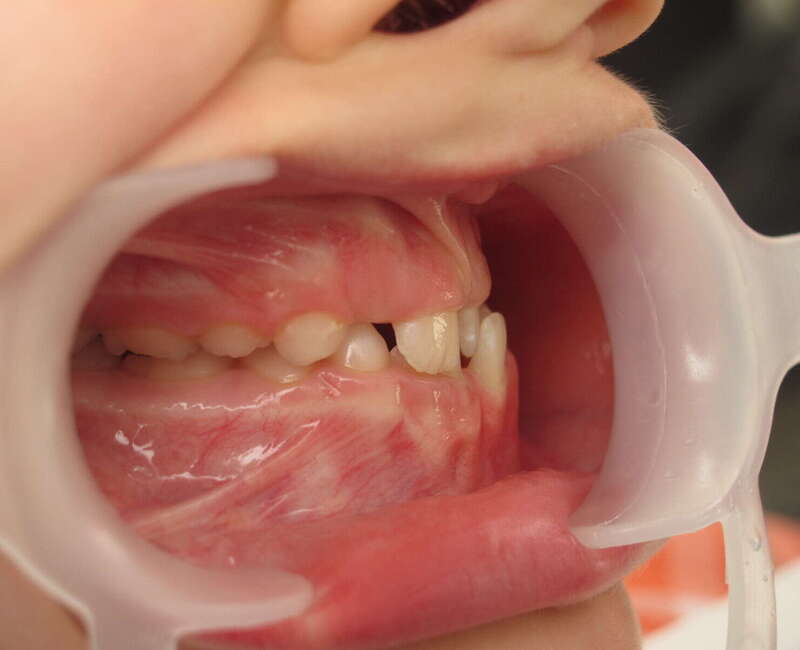

Cas n°1 traité par aligneurs (interception) - enfant

Ce cas d’interception chez un enfant de 8 ans démontre l'efficacité des aligneurs pour corriger des troubles fonctionnels précoces. Le diagnostic présentait des inversions d'articulé provoquant une déviation de la mandibule vers la gauche et un décalage des milieux.

Grâce à une coopération exemplaire et un traitement totalement indolore, l'expansion de l'arcade a permis de recentrer la mâchoire. Cette intervention a littéralement remis la croissance sur les rails, neutralisant le risque d'asymétrie faciale squelettique.

• Correction fonctionnelle : Recentrage immédiat de la mandibule et des milieux inter-incisifs.

• Prévention : Création d'un environnement favorable pour les dents définitives à venir.

• Bien-être : Approche douce respectant le confort de l'enfant.

C'est une étape fondamentale qui simplifie l'avenir orthodontique du patient tout en garantissant un développement facial harmonieux.